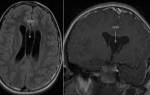

• КТ и МРТ головного мозга для выявления опухолей.